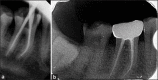

Inappropriate mechanical debridement, persistence of bacteria in the canals and apex, poor obturation quality, over and under extension of the root canal filling, and coronal leakage are some of the commonly attributable causes of failure. Despite the high success rate of endodontic treatment, failures do occur in a large number of cases and most of the times can be attributed to the already stated causes. With an ever increasing number of endodontic treatments being done each day, it has become imperative to avoid or minimize the most fundamental of reasons leading to endodontic failure. This paper reviews the most common causes of endodontic failure along with radiographic examples.